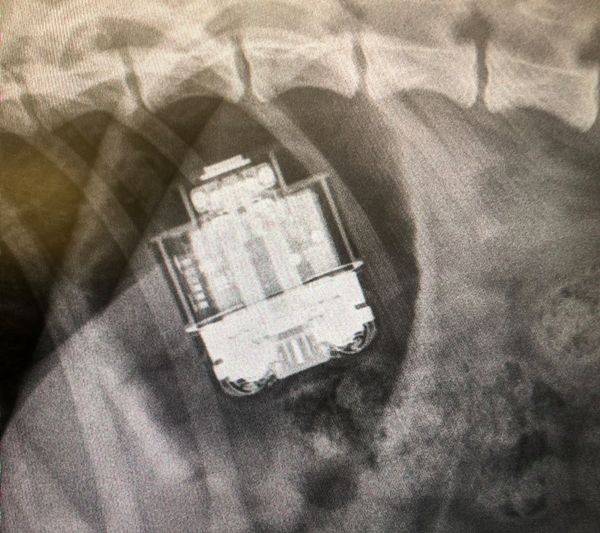

히크 씨는 지미를 데리고 24시간 반려동물 응급실로 달려갔습니다. 그리고 엑스선 촬영 결과 실제로 지미의 소화 기관에서 무선 이어폰 케이스가 발견됐습니다.

수의사는 "강아지를 곧바로 병원에 데려온 것은 정말 잘한 결정"이라며 "충전기 기능이 있는 케이스이기 때문에, 조금만 늦었더라면 배터리가 새어 나가 생명이 위험했을 것"이라고 설명했습니다.

제때 수술해 케이스를 빼낸 덕분에 지미는 건강에 아무런 문제 없이 퇴원할 수 있었습니다. 지미가 삼킨 무선 이어폰과 충전 케이스 역시 흠집 하나 없는 멀쩡한 상태였습니다.

(사진='Vets Now' 페이스북, 홈페이지 캡처)